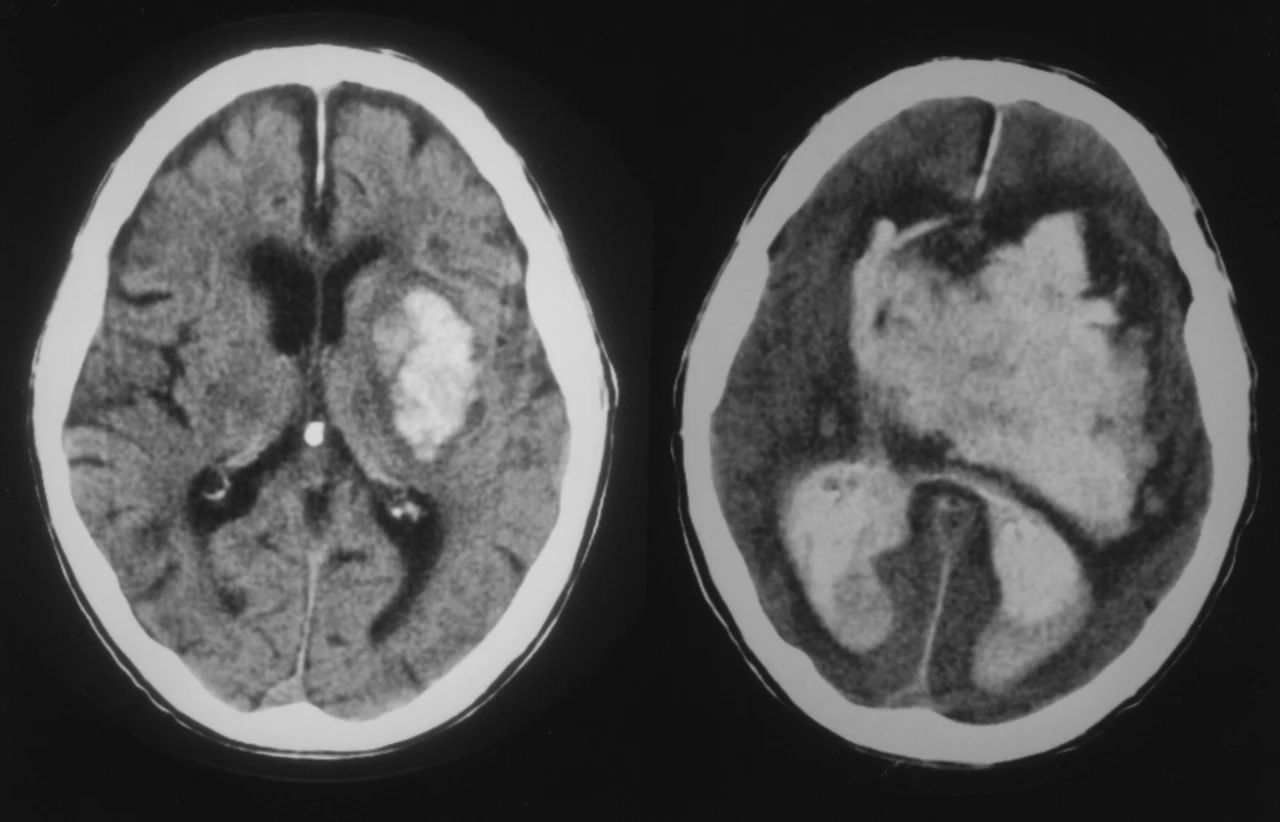

출혈량이 너무 많았다. 뇌수술 적응증에 해당됐다. 두피와 두개골을 잘라내 뇌내출혈을 제거하는 수술. 하지만 가망이 없었다. 수술해도 의식이 돌아올 확률은 없었다. 이미 뇌사에 가까웠기 때문이다.

hs1053258001.jpeg 자발성 뇌출혈의 CT 영상. 우측 사진 정도면 수술해도 의식이 돌아올 가능성이 거의 없는데, 할머니는 더 심했다. 출처는 AHA Stroke 저널의 오리지널 아티클.